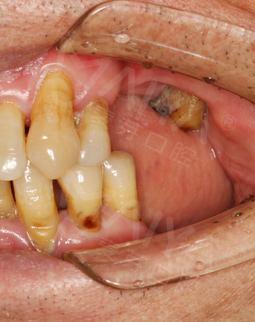

过去的困扰

我叫郭灵声,今年71岁。我的工作就是新闻,来深圳已经26年了,92年人民日报市场报任命我在深圳当办事处主任,就来到深圳,这个城市我看着壮大起来的。十几年前,我就已经安装假牙,但当时技术、条件并不好,假牙用过几年后就脱落了,又在检查过程中查出口腔患有晚期牙周炎,经过拔牙、治疗后,仍然没有达到满意的效果,治疗后的牙冠让我吃东西塞牙、吃东西无味,苦不堪言。

2016年10月 多颗牙缺失,敲定种牙方案

参加过几次活动,也从网络、报纸等媒体一直在关注这里,在一次“幸福晚年有口福”的活动中了解了这里的种牙援助活动,几次实地考察,我接触到郑院长之后,感觉到郑教授不仅医术好,而且非常的亲切和蔼,他能和病人主动沟通交流,知道你想要什么,什么时间做最好,他能给你精准的判断,而且是非常负责任。多方对比之后,还是比较相信这里,相信郑院长的经验和技术,我也顺利地申请到了口福援助。

拍摄了CT,牙齿哪个地方有问题,看的很清楚,非常科学。但是口内有牙周病,需要先治疗再进行种牙,而且他们服务特别好,等待的时候还给倒水,安抚我让我感到很亲切,做了口内全口洁牙+喷砂+抛光+上药去除牙结石,是两个护士给洗的牙,一个细节就能提现这个机构好不好,卫生、环境方面都很不错,我也希望可以早点治疗好,做种植牙!